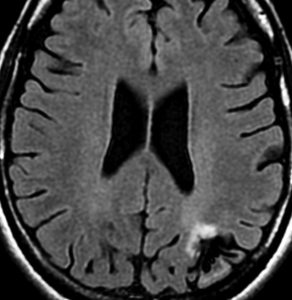

びまん性星細胞腫のIDH 野生型 wild type ゆっくり増大するものがあるか?

無症状で発見されたびまん性星細胞腫です。右側はその6年後,非常に緩徐に増大しています。良性のびまん性星細胞腫グレード2を疑い,手術で周囲脳も含めて完全摘出 supratotal resection しました。病理診断は,びまん性星細胞腫 WHO グレード2,MIB-1は2%,1p/19q欠失なしでした。大学病院の病理部ですが当時はIDHの検査をしていません。

術後4年目のものです。深部に小さな再発像が出現しました。これも予想の範囲内でした。これも手術で全摘出しました。普通ならあとは経過観察をするのみです。

しかし,病理診断では IDH1, IDH2ともに変異なし,野生型 wild typeでした。1p/19q non-codel, ATRX mutantです。急速な悪性化が懸念されましたので術後に局所放射線治療を加えました。それ以降は腫瘍再燃はありません。

経過は,IDH mutant diffuse astrocytoma WHO grade 2です。でも,再発像でwild typeでした。malignant transformationなのか?このような例をどう解釈してよいのか不明です。